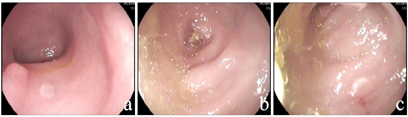

肝功能提示转氨酶升高,血常规提示中性粒细胞和血红蛋白降低。左手腕部正位X线片显示骨龄明显落后于1岁。肠镜检查发现结直肠黏膜糜烂,肠腔内可见较多油性食物残渣附着。全外显子测序显示患儿SBDS基因复合杂合突变,c.258+2T>C来自父亲,为已知致病突变,c.100A>G来自母亲,尚未报道。

血常规:白细胞4.88×109/L,血红蛋白103 g/L,血小板219×109/L,中性粒细胞计数0.52×109/L;肝功能:谷丙转氨酶256.8 U/L,谷草转氨酶151.6 U/L。铁蛋白升高(848.7 ng/ml),血气分析、肾功能、心肌酶、电解质、血糖、三酰甘油、脂肪酶、凝血功能、体液及细胞免疫功能、铜蓝蛋白、粪常规、腹部彩超均正常,甲状腺功能:甲状腺素62.93 nmol/L,偏低,余正常。骨髓象:有核细胞减少,中性粒细胞减少,红系比例减低,血小板散在聚集可见,淋巴细胞比值增高。粪培养提示菌群失调;自身抗体谱、血尿遗传代谢筛查、巨细胞及EB病毒IgM抗体及DNA、T-SPOT、粪便艰难梭菌毒素检测、叶酸、维生素B12均阴性。左手腕部正位X线片显示骨龄明显落后于1岁(图1)。胃镜示上消化道胃镜检查未见异常;肠镜示结直肠黏膜糜烂样改变,肠腔内可见较多油性食物残渣附着(图2)。胃肠镜病理示:十二指肠黏膜绒毛低平,固有层水肿,淋巴管轻度扩张,散在淋巴细胞、浆细胞浸润。回肠末端黏膜绒毛低平,固有层脉管轻度扩张,淋巴组织增生。大肠黏膜组织慢性炎症,固有层内嗜酸性粒细胞增多,26个/HP(图3)。

实验室检查显示持续或间歇性的中性粒细胞减少是最常见的血液学异常表现,80%的患者会出现贫血,网织红细胞低,24%~88%的患者会出现血小板减少[2],随病情进展可表现为全血细胞减少,并有向骨髓增生异常综合征或急性髓系白血病转化的可能性。本例患儿发病即出现两系降低,需警惕恶性转化的风险。另外,肝脏受累表现为从无症状的转氨酶升高、肝肿大、肝脏脂肪浸润到由于肝纤维化引起的不同形式的持续性慢性肝病,甚至肝硬化、肝衰竭[18]。大多数转氨酶升高患儿随年龄的增长而恢复正常,少数患儿出现转氨酶水平持续升高和肝纤维化。该患儿出现血清谷丙转氨酶升高,排除了由感染、肝毒性药物引起的肝损伤,给予保肝、补液、氨基酸奶粉营养等治疗,病情反复。结合患儿临床表现、实验室检查及基因筛查等综合分析,明确诊断为SDS。此外,除了胰腺外分泌功能障碍外,肠病在某些情况下可能导致症状,胃肠黏膜活检提示超过50%的有症状SDS患儿中,十二指肠组织学显示从绒毛钝化到绒毛萎缩及不同程度的炎性改变[19],亦有合并克罗恩病的报道[20]。本例患儿肠镜示结直肠黏膜点片状糜烂,肠黏膜病理示绒毛低平,固有层水肿,淋巴管轻度扩张,大肠黏膜组织慢性炎症,固有层内嗜酸性粒细胞增多,结合患儿有腹泻、便血,曾考虑小肠淋巴管扩张症及过敏性肠炎,给予更换氨基酸奶粉及富含中链脂肪酸的深度水解配方粉治疗效差,故临床上碰到难治性腹泻、生长发育缓慢、中性粒细胞减少、肝酶异常的病例,肠黏膜病理示绒毛低平,淋巴管轻度扩张,除外常见疾病,应考虑到SDS的可能,尽早行基因学检查明确诊断。